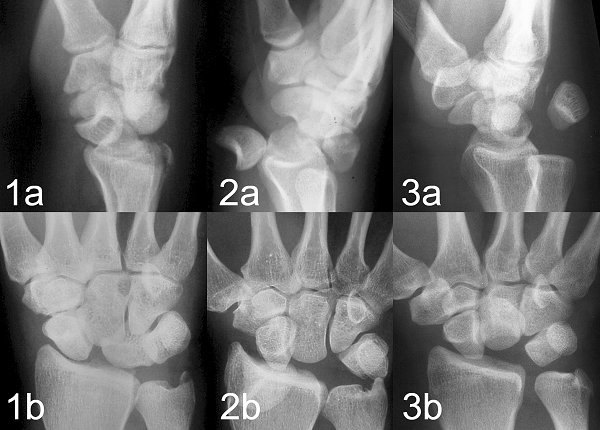

Figure Legend: Lunate dislocations may

be missed in the emergency room through failure to recognize the typical

states are"spilled teacup" sign on the lateral wrist x-ray (1a), hand and

abnormalities which are not dramatic on the PA film (1b). It is unusual

for the lunate to be displaced enough to be obvious to the untrained eye

and in these examples of complete volar (2) and dorsal (3) lunate dislocations.